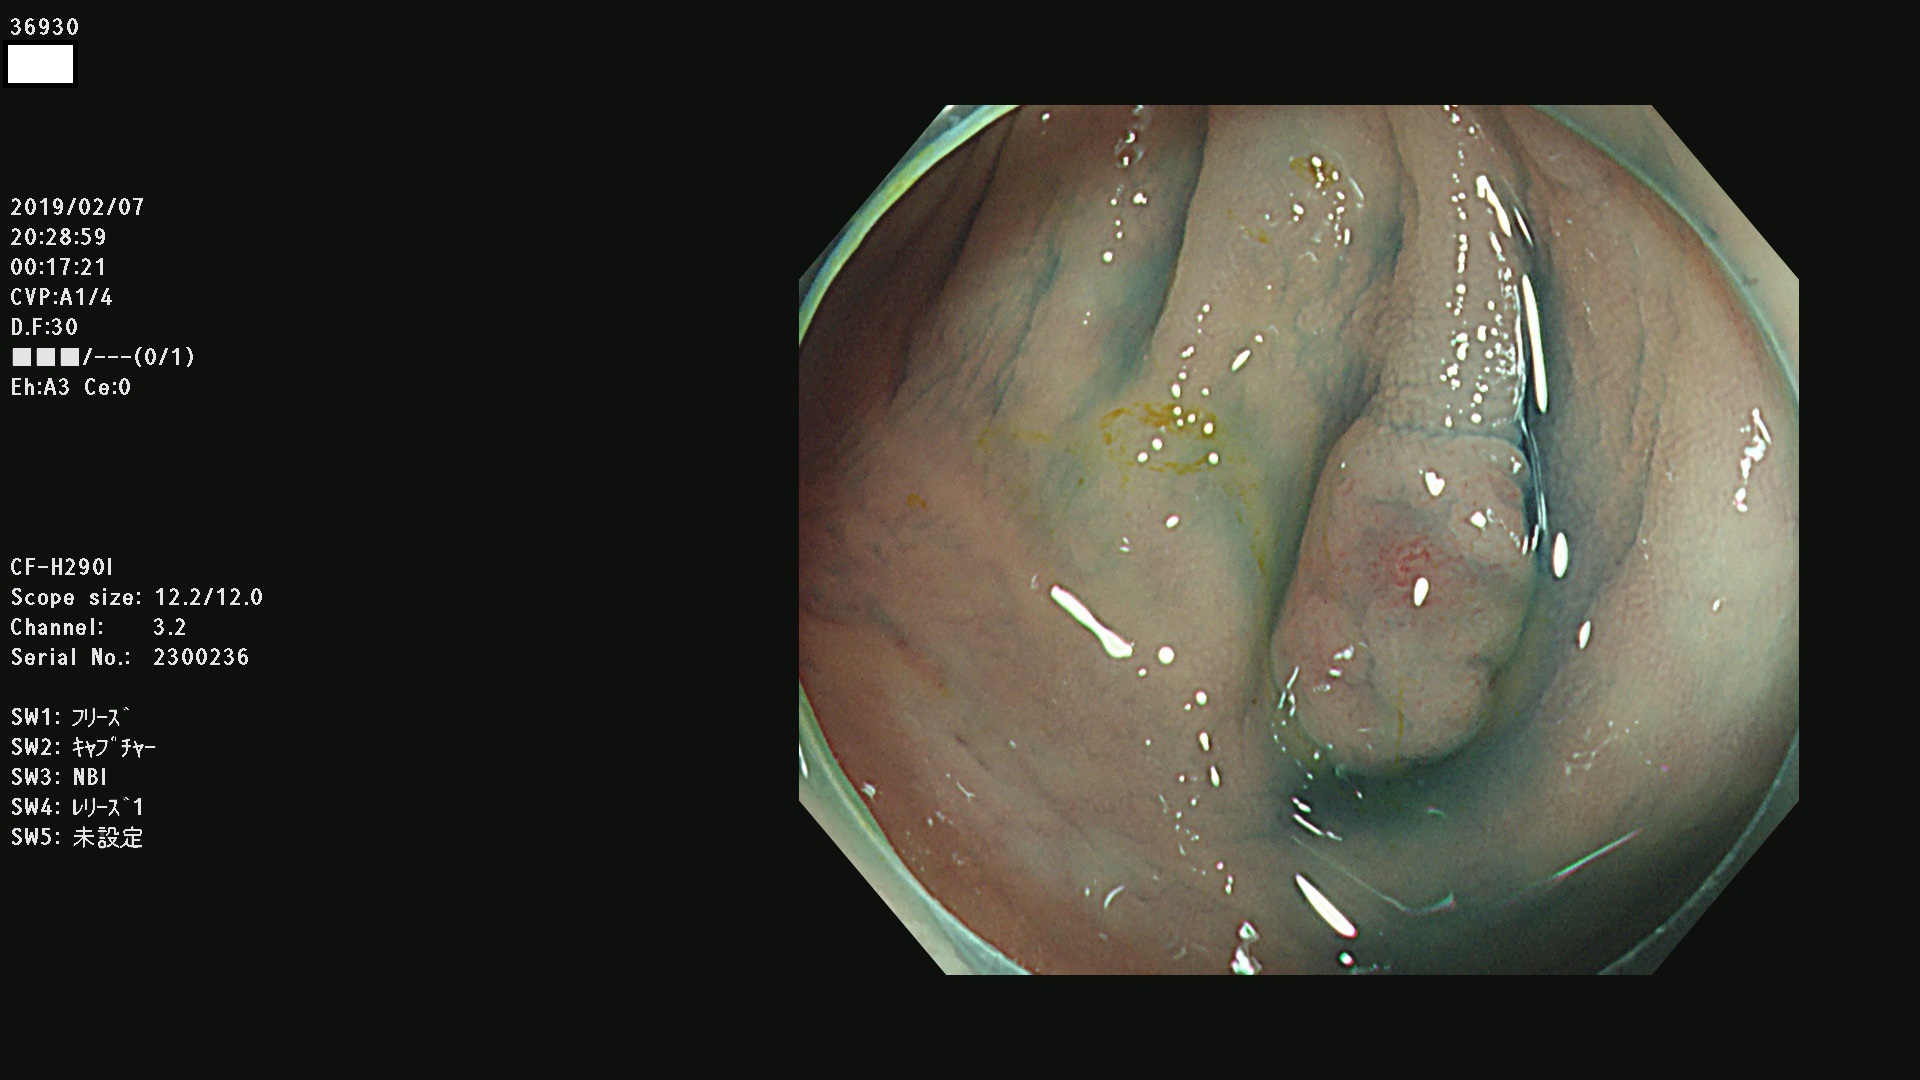

腺腫発見率 67 % (カルテ番号 36900〜36999の100名の方の検査結果で集計)大腸癌検診最新情報

以下のカルテ番号の方に腺腫(Adenoma,Group3〜5)が見つかりました(集計法)

36900 36901 36903 36904 36905 36908 36909 36910 36911 36913 36914 36915 36916 36917 36918 36919 36920 36923 36924 36925 36927 36928 36930 36931(SSAPのみ) 36933 36935 36936 36937 36941 36943 36944 36945 36946 36949 36951 36953 36954 36955 36957 36963 36965 36966 36967 36968 36969 36970 36974 36975 36976 36977 36978 36979 36980 36981 36983 36984 36986 36987 36988 36989 36990 36991 36993 36994 36996 36998 36999

発見困難で危険性の高い平坦型病変(上記100名より抽出) ![]()